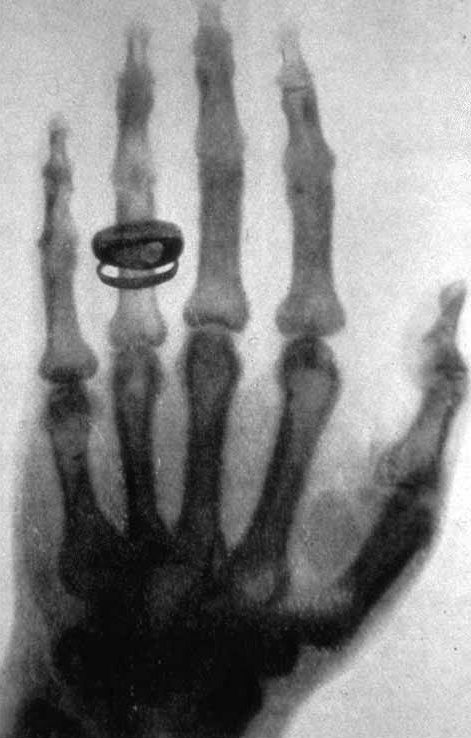

伦琴夫人的手骨

使伦琴更为惊讶的是,当他把手放在纸屏前时,纸屏上竟然留下了手骨的阴影。他意识到这可能是某种特殊的从来没有观察到的射线,它具有特别强的穿透力。于是,当他的妻子因为很久没有见到丈夫,放心不下追到实验室时,伦琴抓起妻子的手,拍下了那幅此后经常在教科书和博物馆展出的照片——世界上第一张人类活体骨骼的照片,上面还套着一枚象征爱情的戒指。